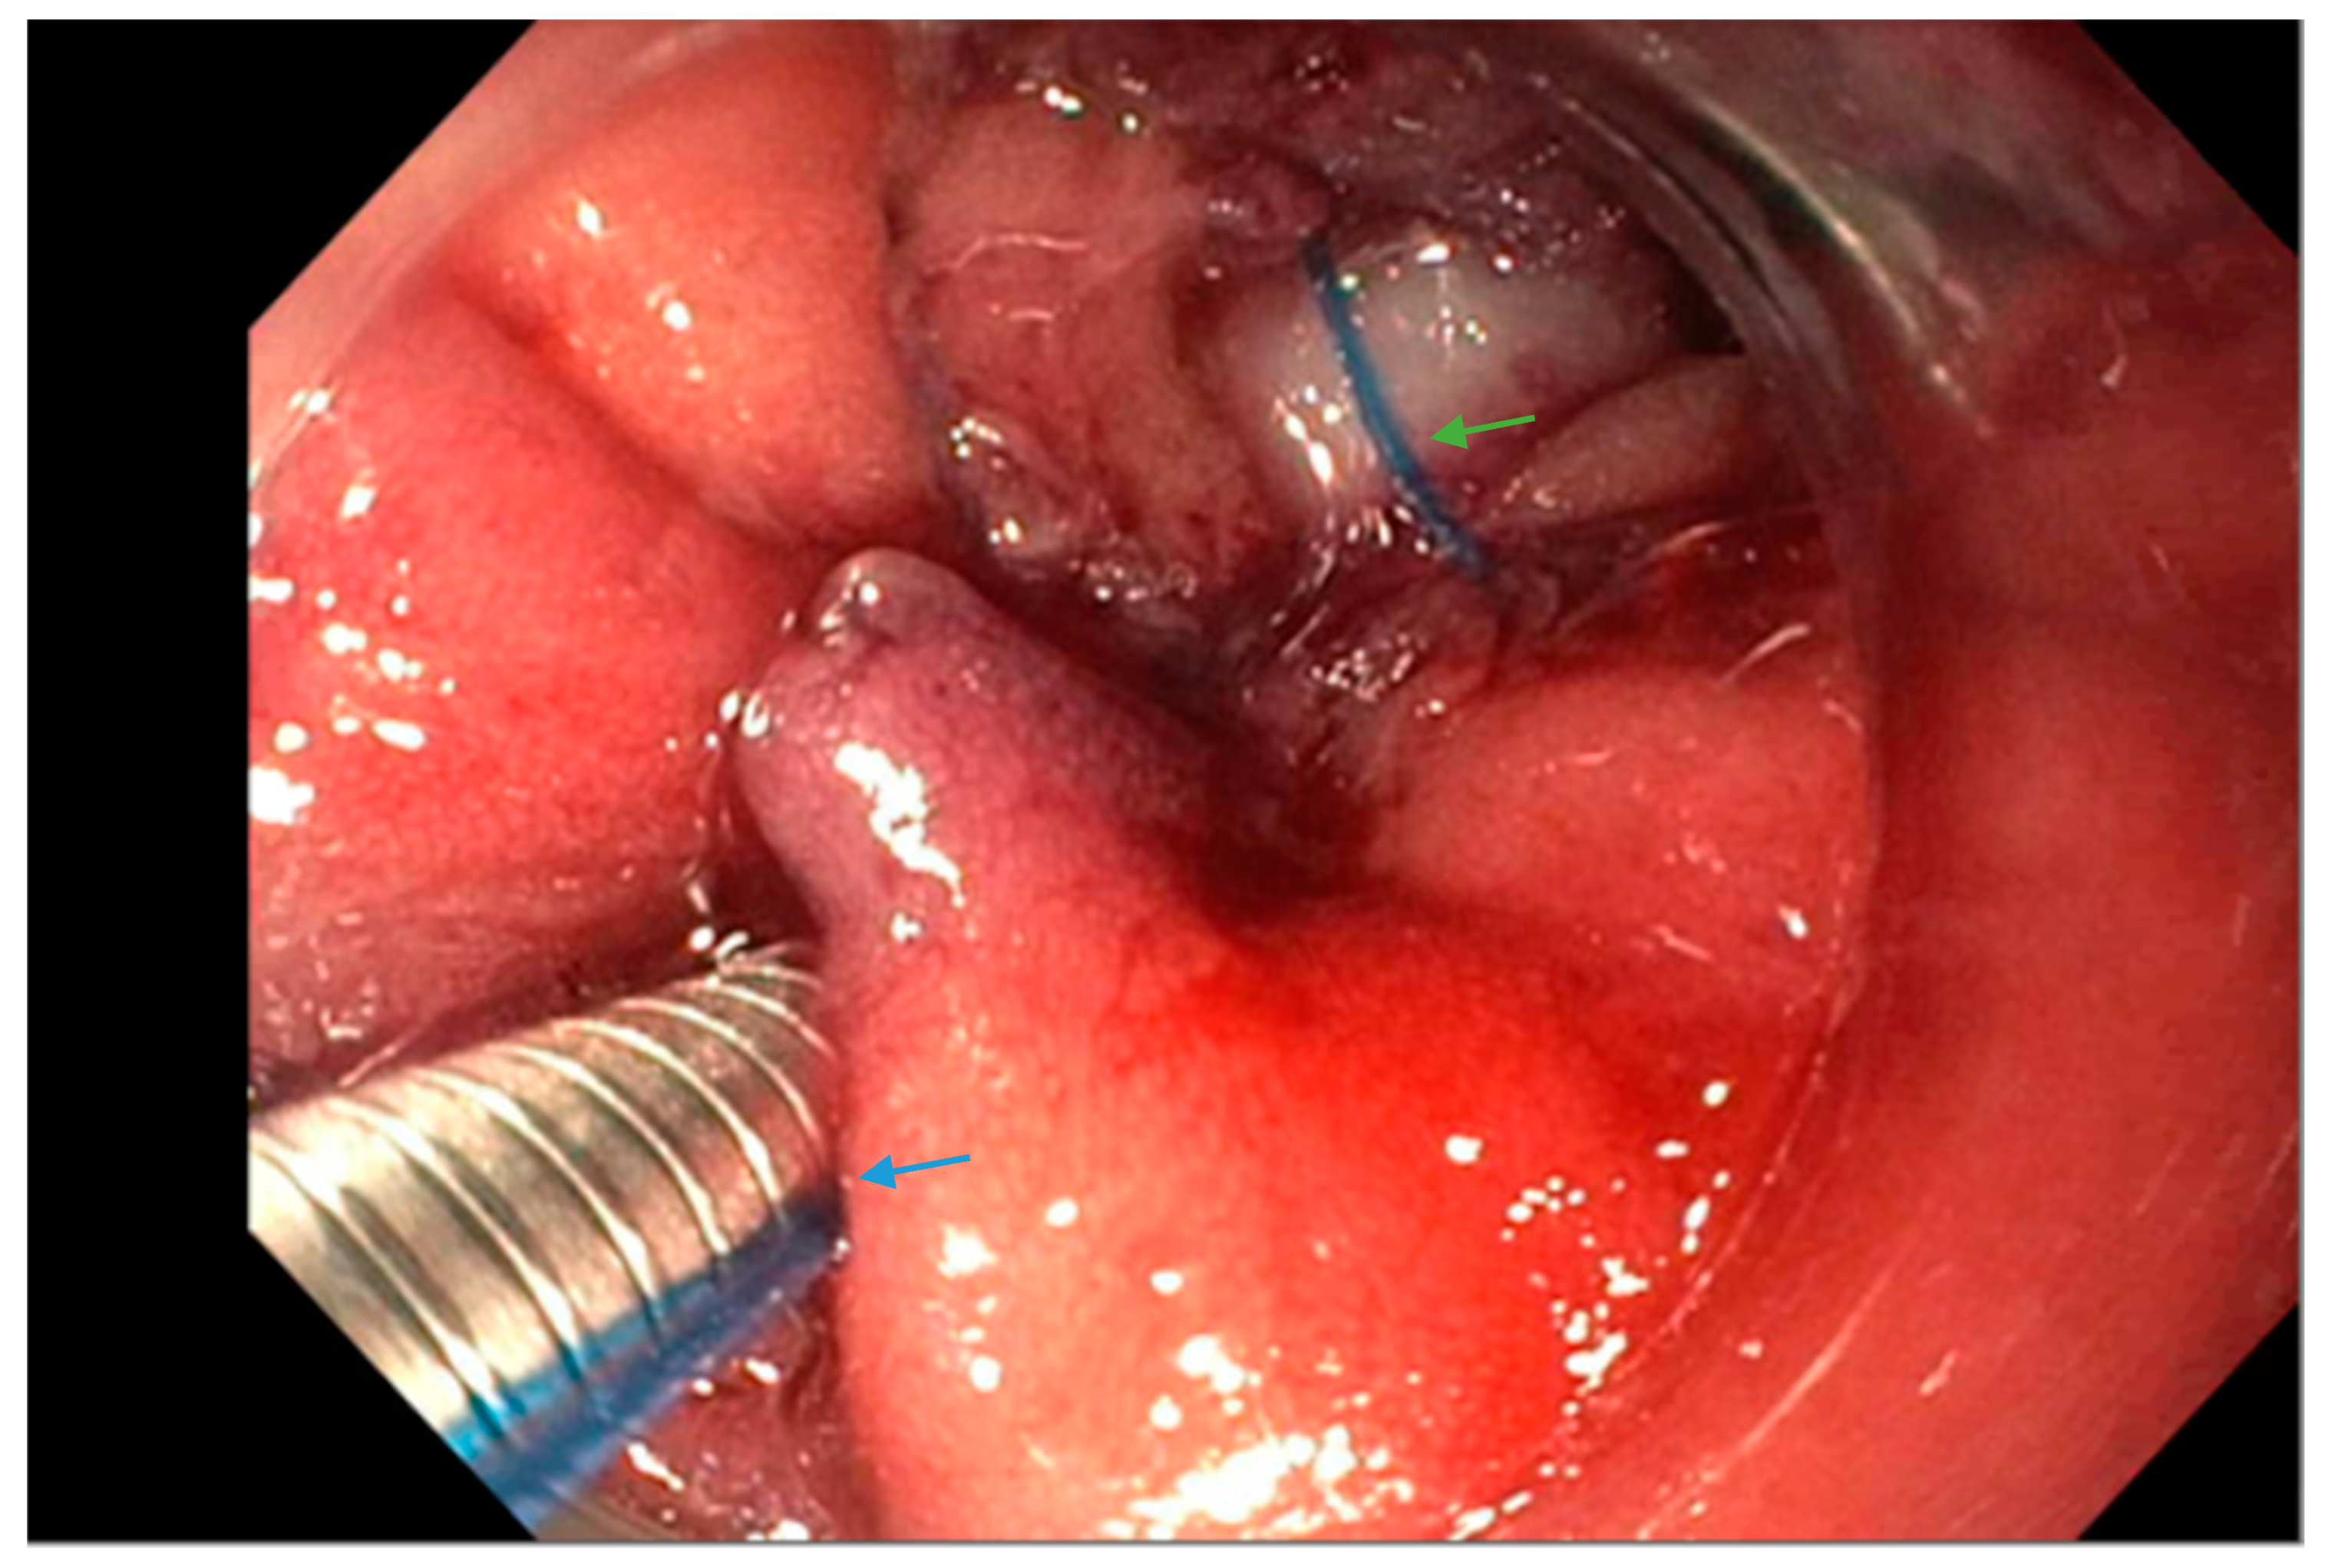

Figure 2.

Upper endoscopy reveals the use of a suturing system (arrow, blue) with a suture in place (arrow, green) at the leak site in a patient following sleeve gastrectomy.